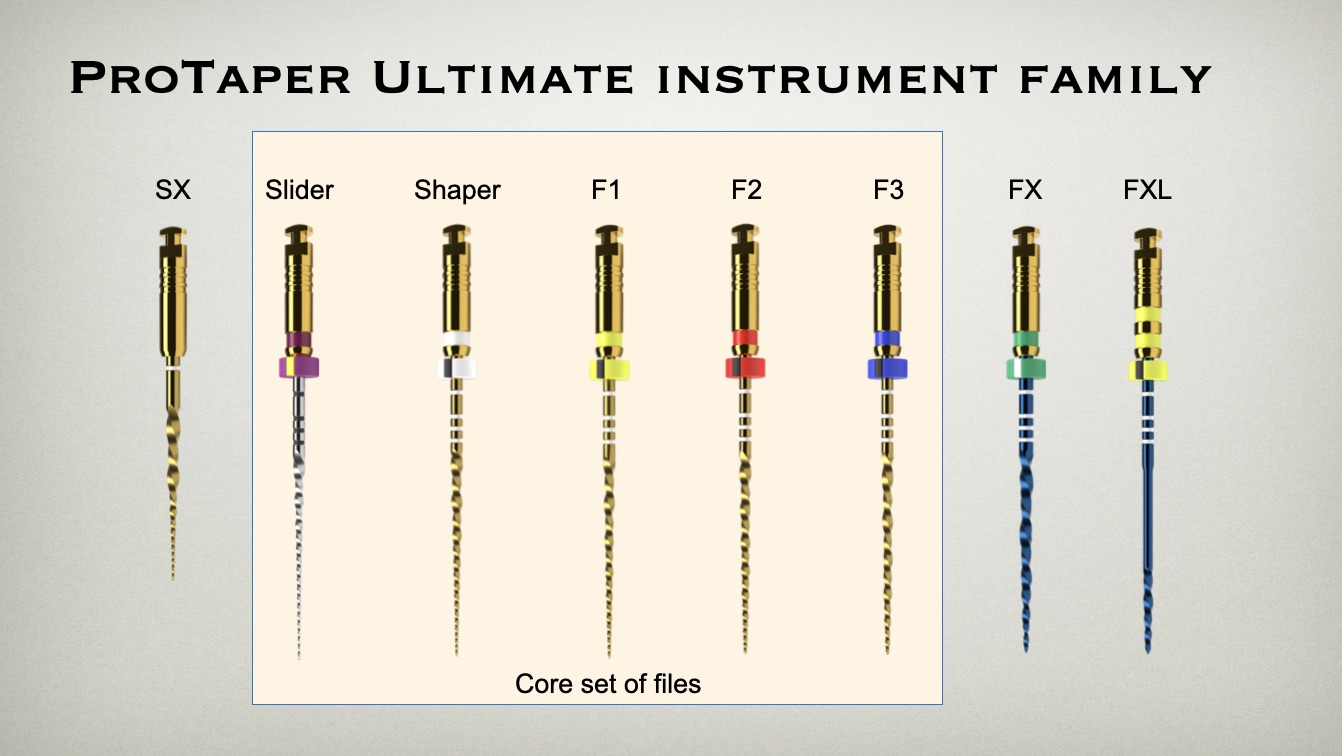

Deep Shape in Endodontics: Significance, Rationale and Benefit

The goal of endodontic treatment is to prevent or cure, when present, Lesions of Endodontic Origin, at times referred to as apical periodontitis. The role of bacteria in the pathogenesis of endodontic disease is well established, and therefore, it is critical to eradicate these pathogens by employing the highest level of presently developed standards. This … Read more